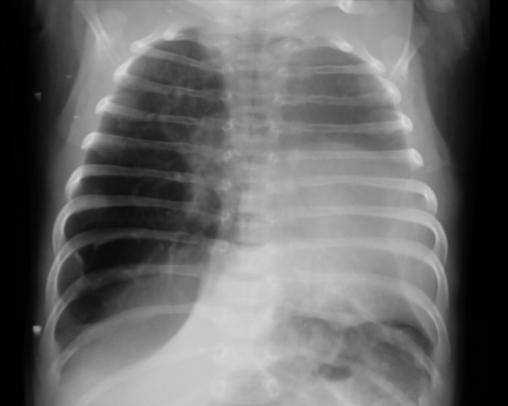

Un nouveau-né âgé de 1 mois est admis aux urgences pédiatriques pour prise en charge d’une détresse respiratoire. Le début de la symptomatologie remonte à la naissance, par l’installation d’une polypnée s’aggravant lors des cris et de l’alimentation, associée à des épisodes de toux sèche. L’examen clinique trouve un nouveau-né tachypnéique, cyanosé avec tirage intercostal et bombement de l’hémithorax droit associé à un wheezing auscultatoire et une SaO2 à 90 % à l’air ambiant. Le patient est mis sous oxygénothérapie et une radiographie thoracique est réalisée, objectivant une hyperaération de l’hémichamp pulmonaire droit refoulant le médiastin (fig. 1). Un scanner est effectué sans injection de produit de contraste et sans sédation, montrant une hyperclarté hypovasculaire avec une expansion du lobe supérieur gauche, refoulant le médiastin et la trachée à gauche, associée à une atélectasie du lobe inférieur droit et de l’hémichamp pulmonaire controlatéral (fig. 2). L’ensemble des éléments radio-cliniques plaident en faveur d’un emphysème lobaire géant compressif congénital (ELGC). Une lobectomie supérieure droite est réalisée, avec une bonne évolution clinique.

Le scanner est plus utile pour analyser l’emphysème, en montrant un lobe distendu, hyperclair, avec une raréfaction vasculaire. Les autres lobes sont beaucoup plus denses, car faiblement aérés et collabés. En cas de volumineux emphysème, il existe souvent une hernie rétrosternale du lobe atteint vers le côté opposé. La tomodensitométrie (TDM) joue un rôle fondamental pour éliminer un emphysème obstructif secondaire à une compression extrinsèque de la bronche par une masse médiastinale, plus exceptionnellement, secondaire à une lésion bronchique endoluminale.6